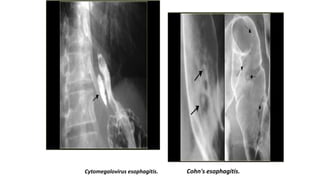

Cytomegalovirus esophagitis. Cohn's esophagitis.

Cytomegalovirus esophagitis

• Cytomegalovirus esophagitis in a patient with AIDS

• Double contrast esophagram shows a large flat ulcer in profile (large arrows) in the midesophagus

with a cluster of small satellite ulcers (small arrows)